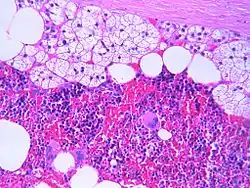

Microscopic features

The typical microscopic features of myelolipomas are shown in the image. There is a mixture of normal adrenal tissue, fat, and a full trilineage maturation of the three major blood-forming elements: myeloid (white blood cell forming), erythroid (red blood cell forming), and megakaryocytic (platelet forming) lines.[1]